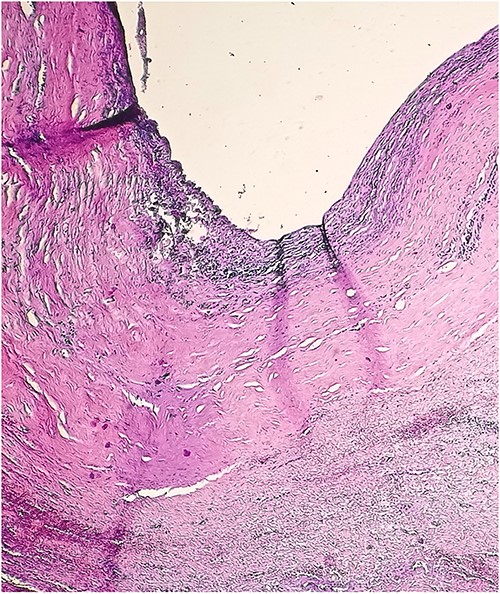

A 46-year-old male presented with mild abdominal pain for the last 2 months. The pain was generalized, recurrent and did not relieve on medication. The patient showed intermittent claudication in his right leg. He presented with a similar complaint five years ago; abdominal pain and urinary urgency and hesitancy, which led to a diagnosis of a simple abdominal cyst. Past medical history was insignificant. Surgical history included retroperitoneal cystectomy, herniorrhaphy and a cleft palate repair. Patient had no other complaints and was not on any medications. He was a smoker with a 22 pack-year smoking history. His temperature was normal, and there was no history of weight loss or loss of appetite or change in bowel movement. On physical examination, the abdomen was soft and non-tender without distention. There was a palpable mass in his right flank. Vital signs and blood tests were within normal limits. Abdominal ultrasound (US) showed a large fluid-filled cystic lesion (Fig. 1a). Subsequent computerized tomography (CT) of the abdomen showed a large, well-defined, clear fluid-filled cyst measuring 17 × 11 × 10 cm, located in the retroperitoneum abutting the lower half of the right kidney, extending to the pelvis and compressing the inferior vena cava (Fig. 1b). Patient was cleared for surgery. Surgical exploration showed several adhesions surrounding the cyst. The cyst was partially isolated from the right ureter and iliac vein and artery (Fig. 2a and b), then surgical excision of 90% of the cyst was performed (Fig. 3). Histopathological report found the cystic wall composed of fibrous connective tissue and lined by one layer of flat cells, with mild lymphocytic infiltrate and congested blood vessels confirming the diagnosis of a chylolymphatic cyst (Fig. 4). On a 1-year follow-up, the patient appears to be recovered and in good health with no recurrence.